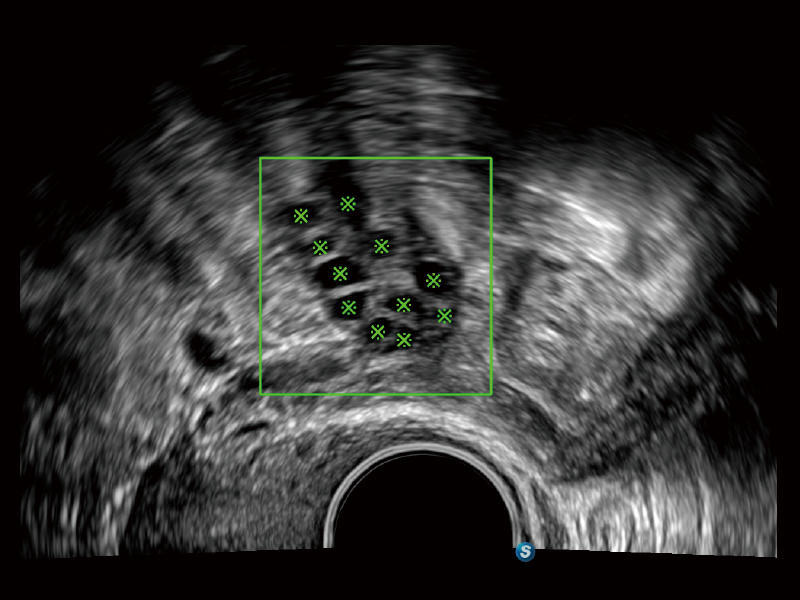

通過(guò)創(chuàng)新的Matrix E自適應(yīng)濾波算法,能有效濾除軟組織和噪聲信號(hào),最大限度保留超低速微細(xì)血流的信號(hào);結(jié)合超長(zhǎng)時(shí)間域算法,極大提升細(xì)微血流的敏感性和空間分辨率,更真實(shí)的反應(yīng)組織、包塊的血流灌注情況。